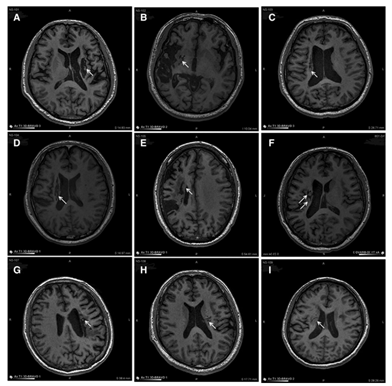

解放军总医院在《干细胞转化医学》杂志上公布了一项研究:9 名 30-65 岁的脑卒中偏瘫患者,在中风后 5-24 个月接受了人源神经干细胞 NSI-566 的脑内回输(注入梗塞灶附近)。经过 24 个月随访,影像学显示干细胞植入区长出了新的神经组织;

随后他接受了脑室间充质干细胞移植:3 周后首次移植,1 个月、2 个月时再次移植,全程无不良反应。随访结果令人惊喜:3 个月、6 个月、12 个月时,他的 NIHSS(国家卫生研究所卒中量表)评分从 23 分分别降至 20 分、19 分、19 分;12 个月时,他已能坐在轮椅上,成功脱离气管切开管和鼻胃管,影像学还显示枕部梗死面积和血肿周围低密度区域明显缩小。